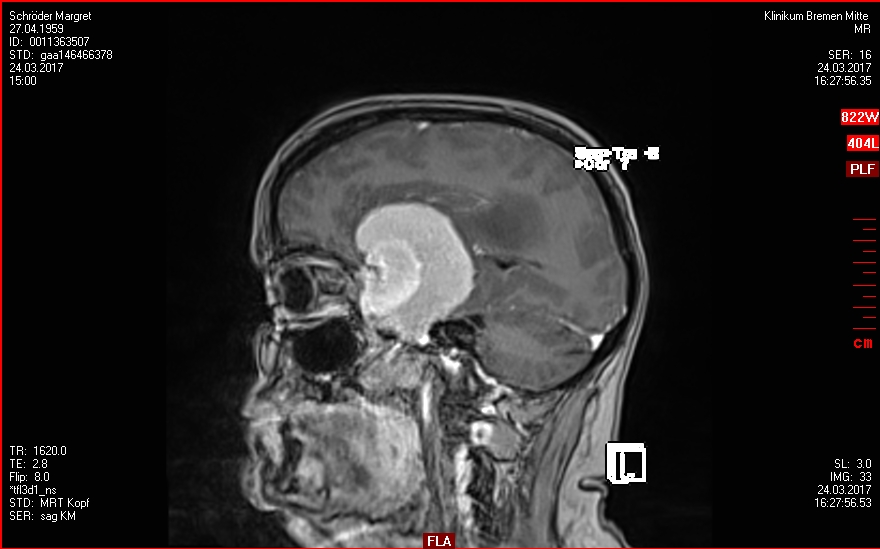

Dies ist nur eine kleine Zusammfassung meiner Meningenom-Geschichte (Tumore im Kopf die von den Hirnhäuten ausgehen und deshalb keine Hirntumore sind).

- Begonnen hat es nach der OP im Jahr 2017 mit ein paar Ausfällen. Schon ziemlich erschreckend als sich da ein riesiges Ding im Kopf befand, was da nicht sein sollte. Aber es konnte erfolgreich operiert werden und auch die Reha hat prima geklappt.

- In 2021 wurde ein Rezidiv gefunden und erfolgreich im Gamma-Knife bestrahlt.

- Und Ende 2024 war eine neue OP notwendig, in der vier Rezidive entfernt wurden. Vier weitere wurden Anfang 2025 im Gamma-Knife erfolgreich bestrahlt.

Vor 12 Monaten mussten meine Tumore im Kopf operiert werden. Die Operation war erfolgreich, aber die entnommenen Tumoren waren böse und es gab weitere Tumore, die im Gamma-Knife bestrahlt wurden. Dabei fand sich ein neuer Tumor, der später nicht mehr auffindbar war, einer anderer schien gewachsen zu sein. Und auch die Art der Behandlung/Bestrahlung war unklar. Mittleres Durcheinander. Aber das neueste MRT vom 10. November zeigt, dass es weitere Tumore in meinem Kopf gibt, die bestrahlten sind größenstabil. Ein paar kleine sind im Sommer dazu gekommen, aber seit August nicht weiter gewachsen. Eine bessere Diagnose war wohl nicht möglich. Und ich habe keinerlei Symptome. Die Mediziner haben es nicht leicht – aber ich sehr dankbar für ihre Hilfe.